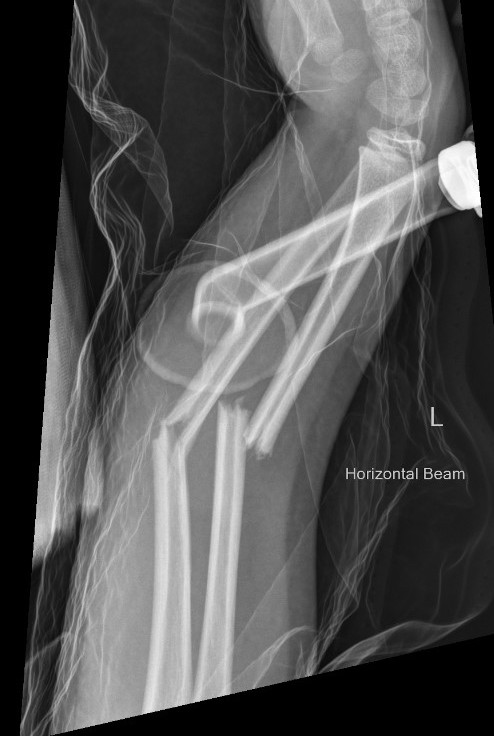

3. Intramedullary elastic nail

TENS technique

Technique

Radius (typically first as more difficult to reduce)

Entry point with awl 2 cm proximal to distal physis

1. Radial styloid / distal lateral entry

- ensure radial nerve / cephalic vein, 1st extensor compartment protected

2. Listers tubercle / dorsal entry

Elastic Nail size

60 - 70% of the intramedullary canal

Typically 1.5 - 2.5 mm

Fracture reduction

Avoid passing nails incorrectly multiple times as may cause compartment syndrome

Bend tip of elastic nail

May need small open reduction

Cut nail

Withdraw 1 cm, cut with endcutter, then advance

Ulna (usually reduced after radius fixation)

Entry point 2 cm distal to apophyseal plate

1. Proximal lateral

- avoids ulna nerve

3. Distal medial

Postoperative

Cast in supination to tighten interosseous membrane

Cast 6 weeks

Removal of TENS at 4 - 6 months once osseous union established